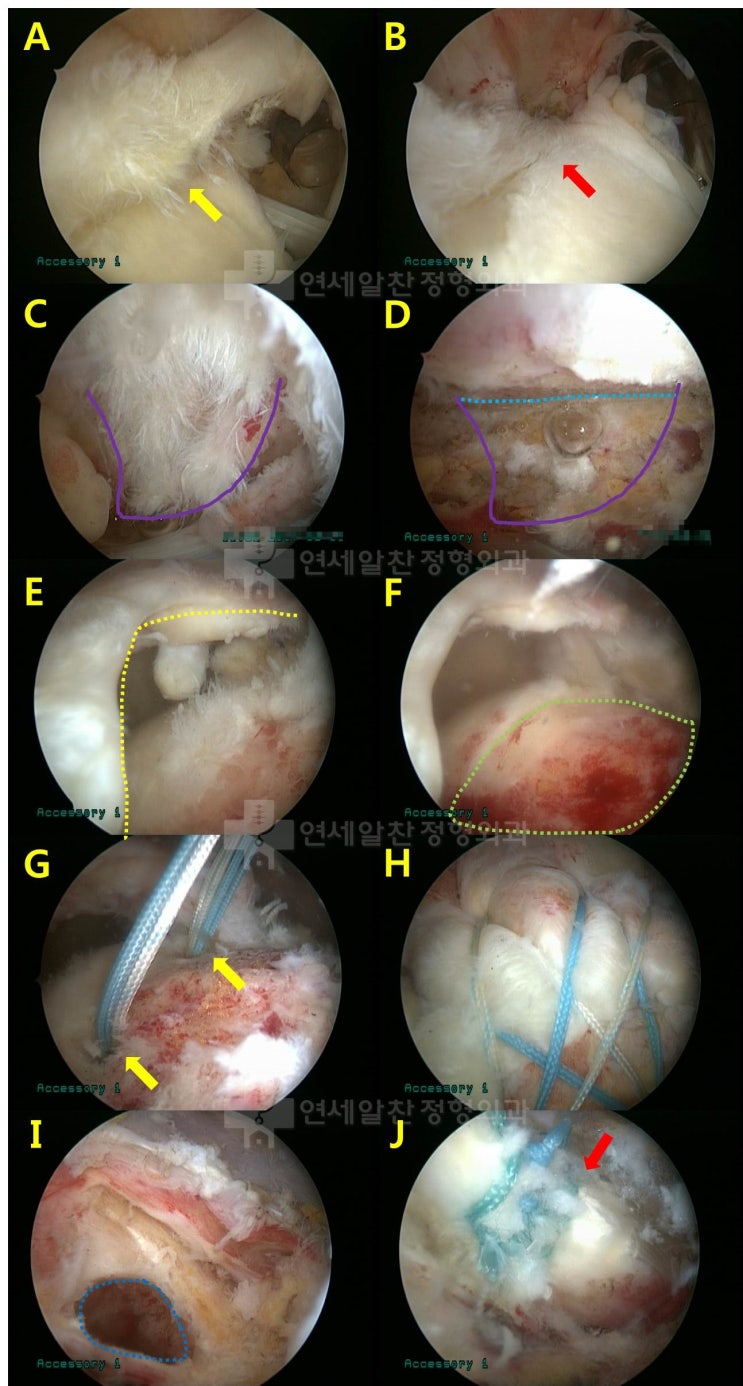

어깨 회전근개 파열 : 보다 단단하게 봉합하는 이열봉합법

안녕하세요. 정형외과 전문의 이동규 입니다. 오늘은 회전근개 파열에서 관절경 수술시 더 단단하게 봉합하...